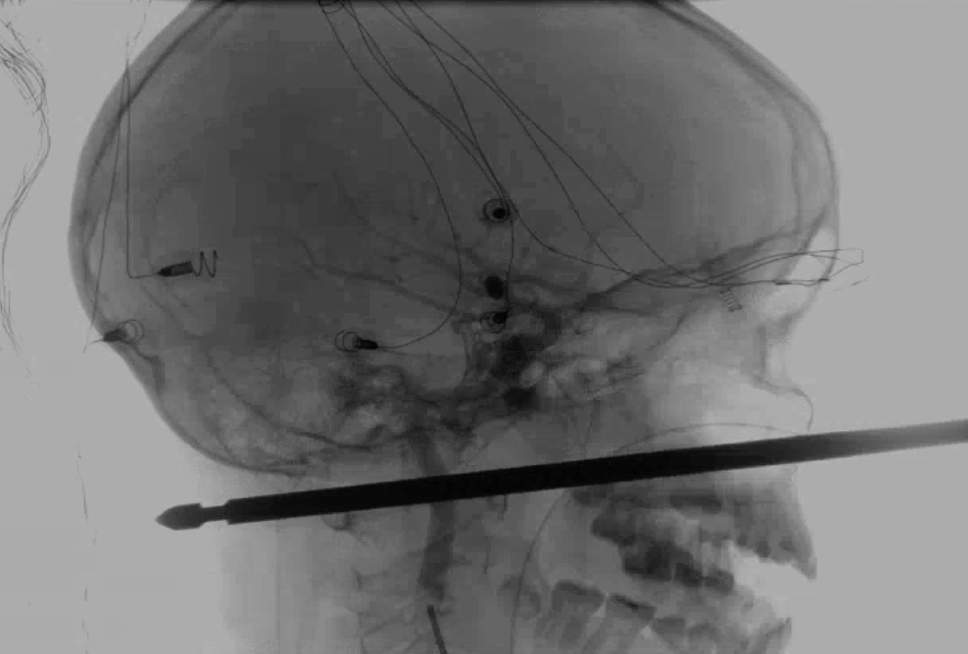

E’ avvenuto in America, nel Missouri. Un bambino di 10 anni, Xavier Cunningham,  per sfuggire a delle vespe è caduto dalla casa sull’albero della sua casa e la sua testa è stata trapassata da uno spiedino da barbecue: lo spiedo è entrato vicino al naso ed è uscito sulla nuca.

Un incidente che sarebbe potuto essere fatale, ma che fortunatamente non lo è stato: lo spiedo non ha intaccato nessun organo vitale.

I medici parlano di miracolo: “Accade una volta su un milione che uno spiedo lungo 15 centimetri passi attraverso la faccia fino al collo senza colpire nulla. Quell’affare gli ha risparmiato l’occhio, il cervello e la spina dorsale. Il bambino è stato molto coraggioso e la sua tranquillità ci ha facilitato il lavoro. Non è una cosa da poco, specialmente se consideriamo che ha dovuto attendere diverse ore per essere operato” ha raccontato Koji Ebersole, direttore del reparto di neurochirurgia endovascolare del Kansas City Hospital.